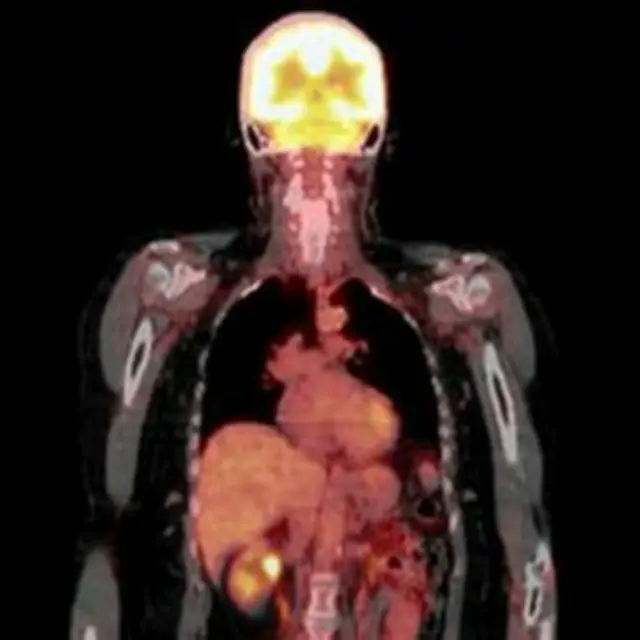

CT (bilgisayarlı tomografi), MRI (emar, manyaetik rezonanslı görüntüleme) ya da PET (nükleer tıbbi görüntüleme) gibi görüntüleme yöntemleri, küçük tümörlerin tespit ve teşhisini mümkün kılıyor.